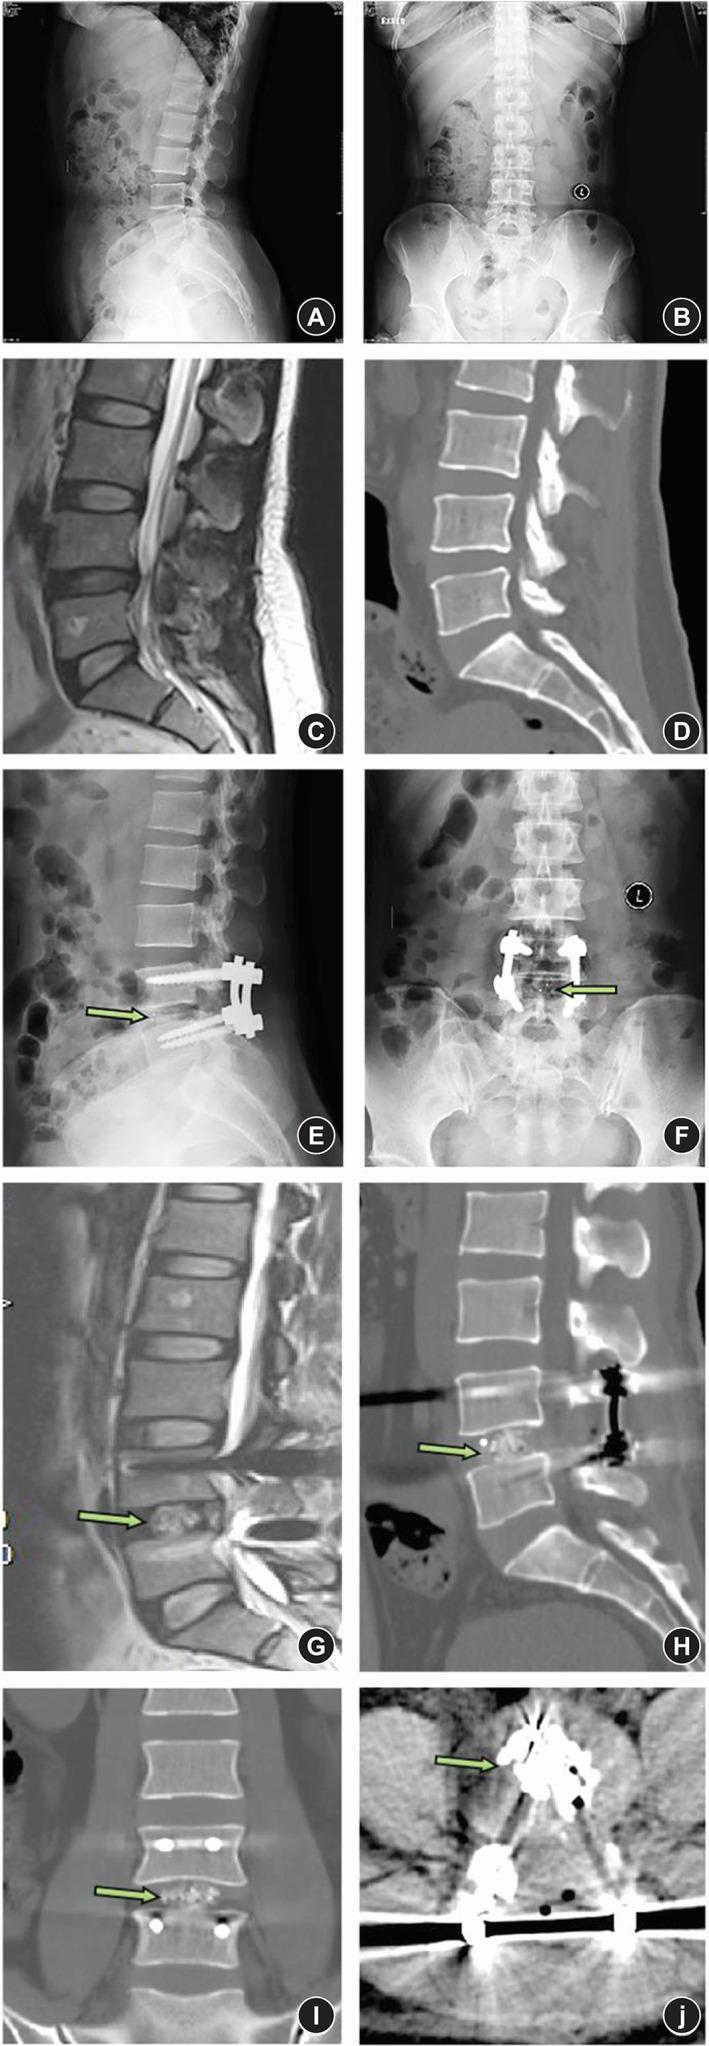

Based on the inclusion and exclusion criteria, the comparative analysis included consecutive patients with grade-1 degenerative spondylolisthesis who underwent oblique LIF (OLIF, n = 36) or minimally invasive transforaminal LIF (MI-TLIF, n = 45) at the Department of Spine Surgery, Beijing Jishuitan Hospital from January 2016 to August 2017. Patient satisfaction Japanese Orthopaedic Association score, visual analog scale (VAS) scores for back and leg pain, Oswestry disability index (ODI), radiographic outcomes including anterior/posterior disc heights (ADH/PDH), foraminal height (FH), foraminal width (FW), cage subsidence, cage retropulsion, and fusion rate were assessed during a 2-year follow-up. Continuous data are presented as mean ± standard deviation and were compared between groups using the independent sample t-test. Categorical data are presented as n (%) and were compared between groups using the Pearson chi-squared test or Fisher's exact test. Repetitive measurement and analysis of variance was employed in the analysis of ODI, back pain VAS score, and leg pain VAS score. Statistical significance was defined as p < 0.05.

The OLIF and MI-TLIF groups comprised 36 patients (age, 52.1 ± 7.2 years; 27 women) and 45 patients (age, 48.4 ± 14.4 years; 24 women), respectively. Satisfaction rates at 2 years post procedure exceeded 90% in both groups. The OLIF group had less intraoperative blood loss (140 ± 36 vs 233 ± 62 mL), lower back pain VAS score (2.42 ± 0.81 vs 3.38 ± 0.47), and ODI score (20.47 ± 2.53 vs 27.31 ± 3.71) at 3 months follow-up (with trends toward lower values at 2 years follow-up), but higher leg pain VAS scores at all postoperative time points than the MI-TLIF group (all p < 0.001). ADH, PDH, FD, and FW improved in both groups post-surgery. At the 2 year follow-up, the OLIF group had a higher rate of Bridwell grade-I fusion (100% vs 88.9%, p = 0.046) and lower incidences of cage subsidence (8.33% vs 46.67%, p < 0.001) and retropulsion (0% vs 6.67%, p = 0.046) than the MI-TLIF group.

根据纳入和排除标准,本回顾性研究纳入了 2016 年 1 月至 2017 年 8 月在北京积水潭医院脊柱外科行 OLIF(n=36)或 MI-TLIF(n=45)治疗的 1 级退变性滑脱患者。在 2 年的随访中,评估患者满意度(日本矫形协会评分)、腰痛和腿痛的视觉模拟评分(VAS)、Oswestry 功能障碍指数(ODI)、影像学结果(包括前/后椎间盘高度[ADH/PDH]、椎间孔高度[FH]、椎间孔宽度[FW]、 cage 下沉、 cage 后移和融合率)。连续数据以均值±标准差表示,采用独立样本 t 检验比较组间差异。分类数据以 n(%)表示,采用 Pearson 卡方检验或 Fisher 确切概率法比较组间差异。采用重复测量方差分析比较 ODI、腰痛 VAS 评分和腿痛 VAS 评分。p 值<0.05 为差异有统计学意义。

OLIF 组和 MI-TLIF 组分别包括 36 例患者(年龄 52.1±7.2 岁,27 例女性)和 45 例患者(年龄 48.4±14.4 岁,24 例女性)。两组术后 2 年的满意度均超过 90%。OLIF 组术中出血量较少(140±36 比 233±62 mL),术后 3 个月时腰痛 VAS 评分(2.42±0.81 比 3.38±0.47)和 ODI 评分(20.47±2.53 比 27.31±3.71)较低(术后 2 年呈下降趋势),但术后各时间点腿痛 VAS 评分均高于 MI-TLIF 组(均 p<0.001)。两组术后 ADH、PDH、FD 和 FW 均得到改善。术后 2 年时,OLIF 组 Bridwell 分级融合率较高(100%比 88.9%,p=0.046),cage 下沉率较低(8.33%比 46.67%,p<0.001)和后移率较低(0%比 6.67%,p=0.046)。